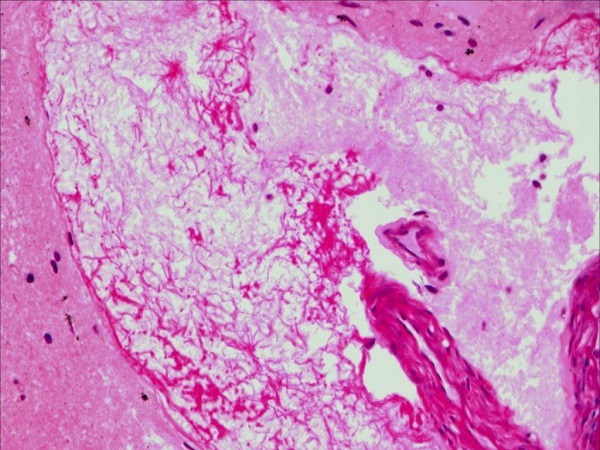

女女骨髓生育其实指的就是从女同性恋中的其中一位女性的骨髓组织中提取出能够制造精子的干细胞,然后通过试管婴儿的方式实现单性别生育。就目前而言,这项骨髓生育技术还没有出来,还处于试验阶段并没有进行临床上的应用,因此不仅仅是上海现在任何国家和城市都是不能够进行骨髓生孩子的。

骨髓生育就是从女性骨髓中提取造精干细胞实现单性别生育